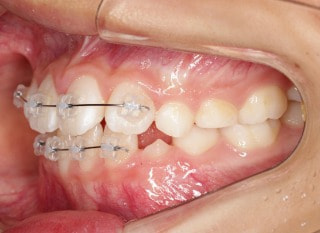

前歯装置装着時

小児期第一段階

終了時